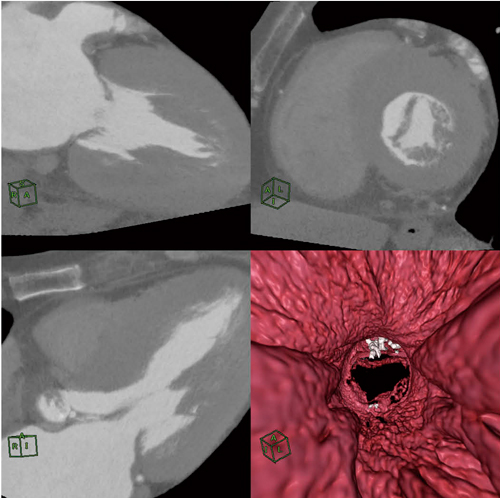

図4 僧帽弁と乳頭筋,および腱索の表示 高速レンダリングが滑らかな画像処理を提供する。

図4 僧帽弁と乳頭筋,および腱索の表示

高速レンダリングが滑らかな画像処理を提供する。